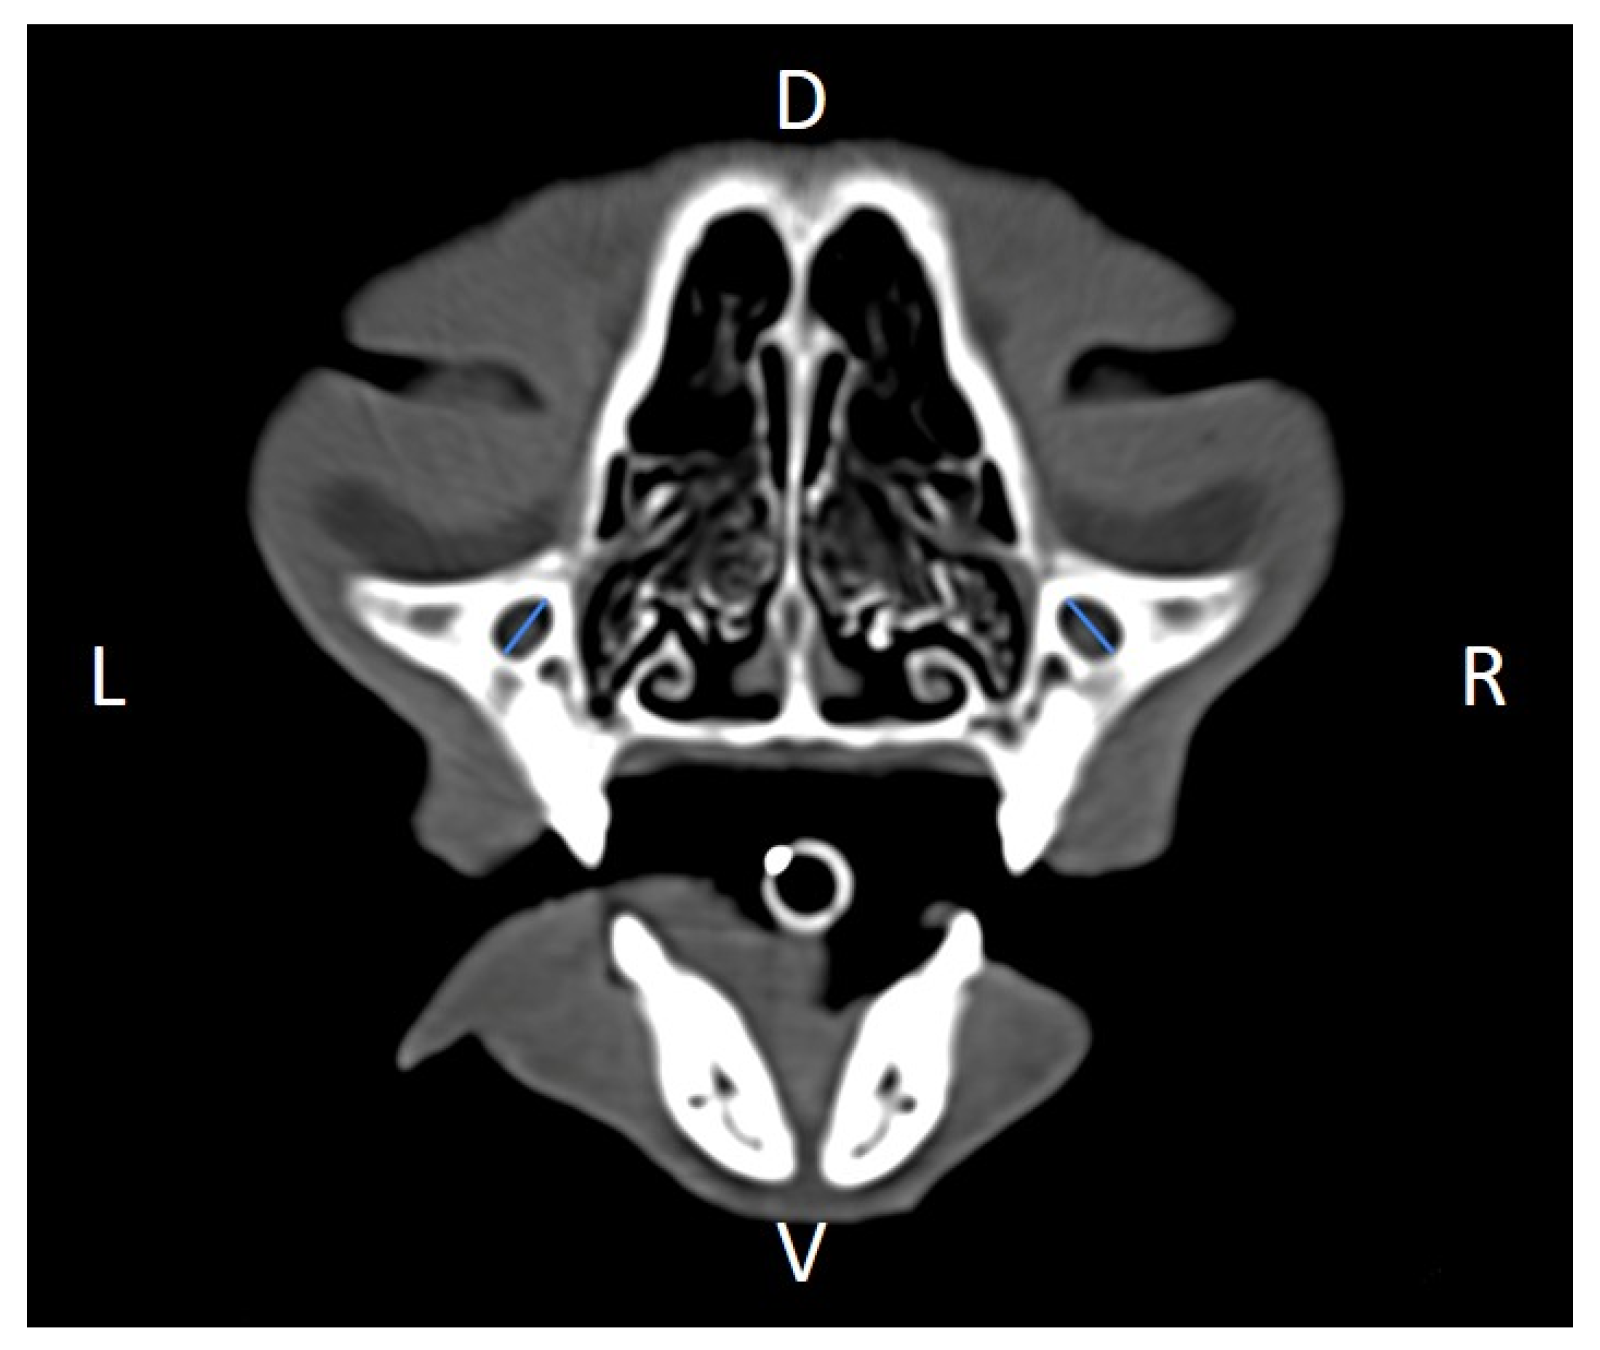

Figure 7. Orbital width (OW) measured at the left and right sides, on a transverse CT image (blue lines). D, dorsal, L, left, R, right, V, ventral.